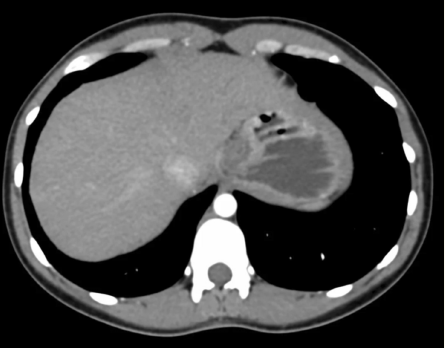

1. La paciente ingresa al servicio de urgencias por persistencia del dolor abdominal a pesar del tratamiento. Se le realiza un estudio de imagen (figura 1). ¿Qué tipo de estudio es?

2. Tomografía computada abdominopélvica simple

3. Tomografía computada abdominopélvica contrastada

Figura 1 Estudio de imagen realizado al ingreso a urgencias